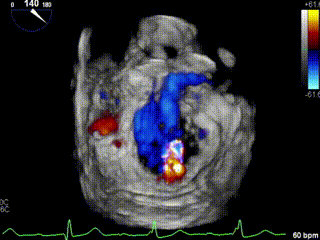

此次手术演示的患者是一名79岁老年女性,既往曾行永久起搏器置入术,合并高血压病、慢性肾脏病等,超声心动图提示“二尖瓣重度反流,A3区脱垂。外科手术高危,STS评分9.71%。

TEE外科视角见偏心反流

术前,王建安教授团队经过充分评估后选用DragonFly器械,术中在超声引导下建立右侧股静脉入路、精准穿刺房间隔,之后继续在经食道超声引导下将瓣膜夹器械输送到左心房,再利用多视角评估瓣膜夹位置和夹合效果。

超声评估少量反流,无残余脱垂,平均跨瓣压差2mmHg。经在场专家讨论后,决定释放二尖瓣瓣膜夹。

最终超声评估显示二尖瓣少量残余反流,二尖瓣平均跨瓣压差2mmHg。患者情况良好,手术顺利完成。